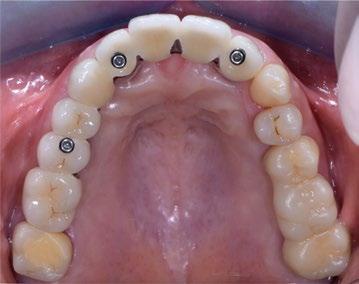

Apical a esta plataforma queda un cuello tratado específicamente (UTM) para su convivencia con el conectivo supracrestal mejorando la estabilidad de dichas futuras fibras gracias a la convergencia a coronal de los 3 mm de cuello y que en los primeros estadios de cicatrización aportan espacio para el biomarterial y el injerto de tejido conectivo sin que existan presiones nocivas (Figuras 6 y 7).

Este cuello convergente hará las veces de pilar intermedio colocado en protocolo de one abutment one time y con la mejor conexión que se puede emplear a ese nivel de profundidad que es la que no existe ya que se trata de un implante intramucoso de una sola pieza, esto genera una gran estabilidad biomecánica y nula filtración bacteriana (Figura 8).

17